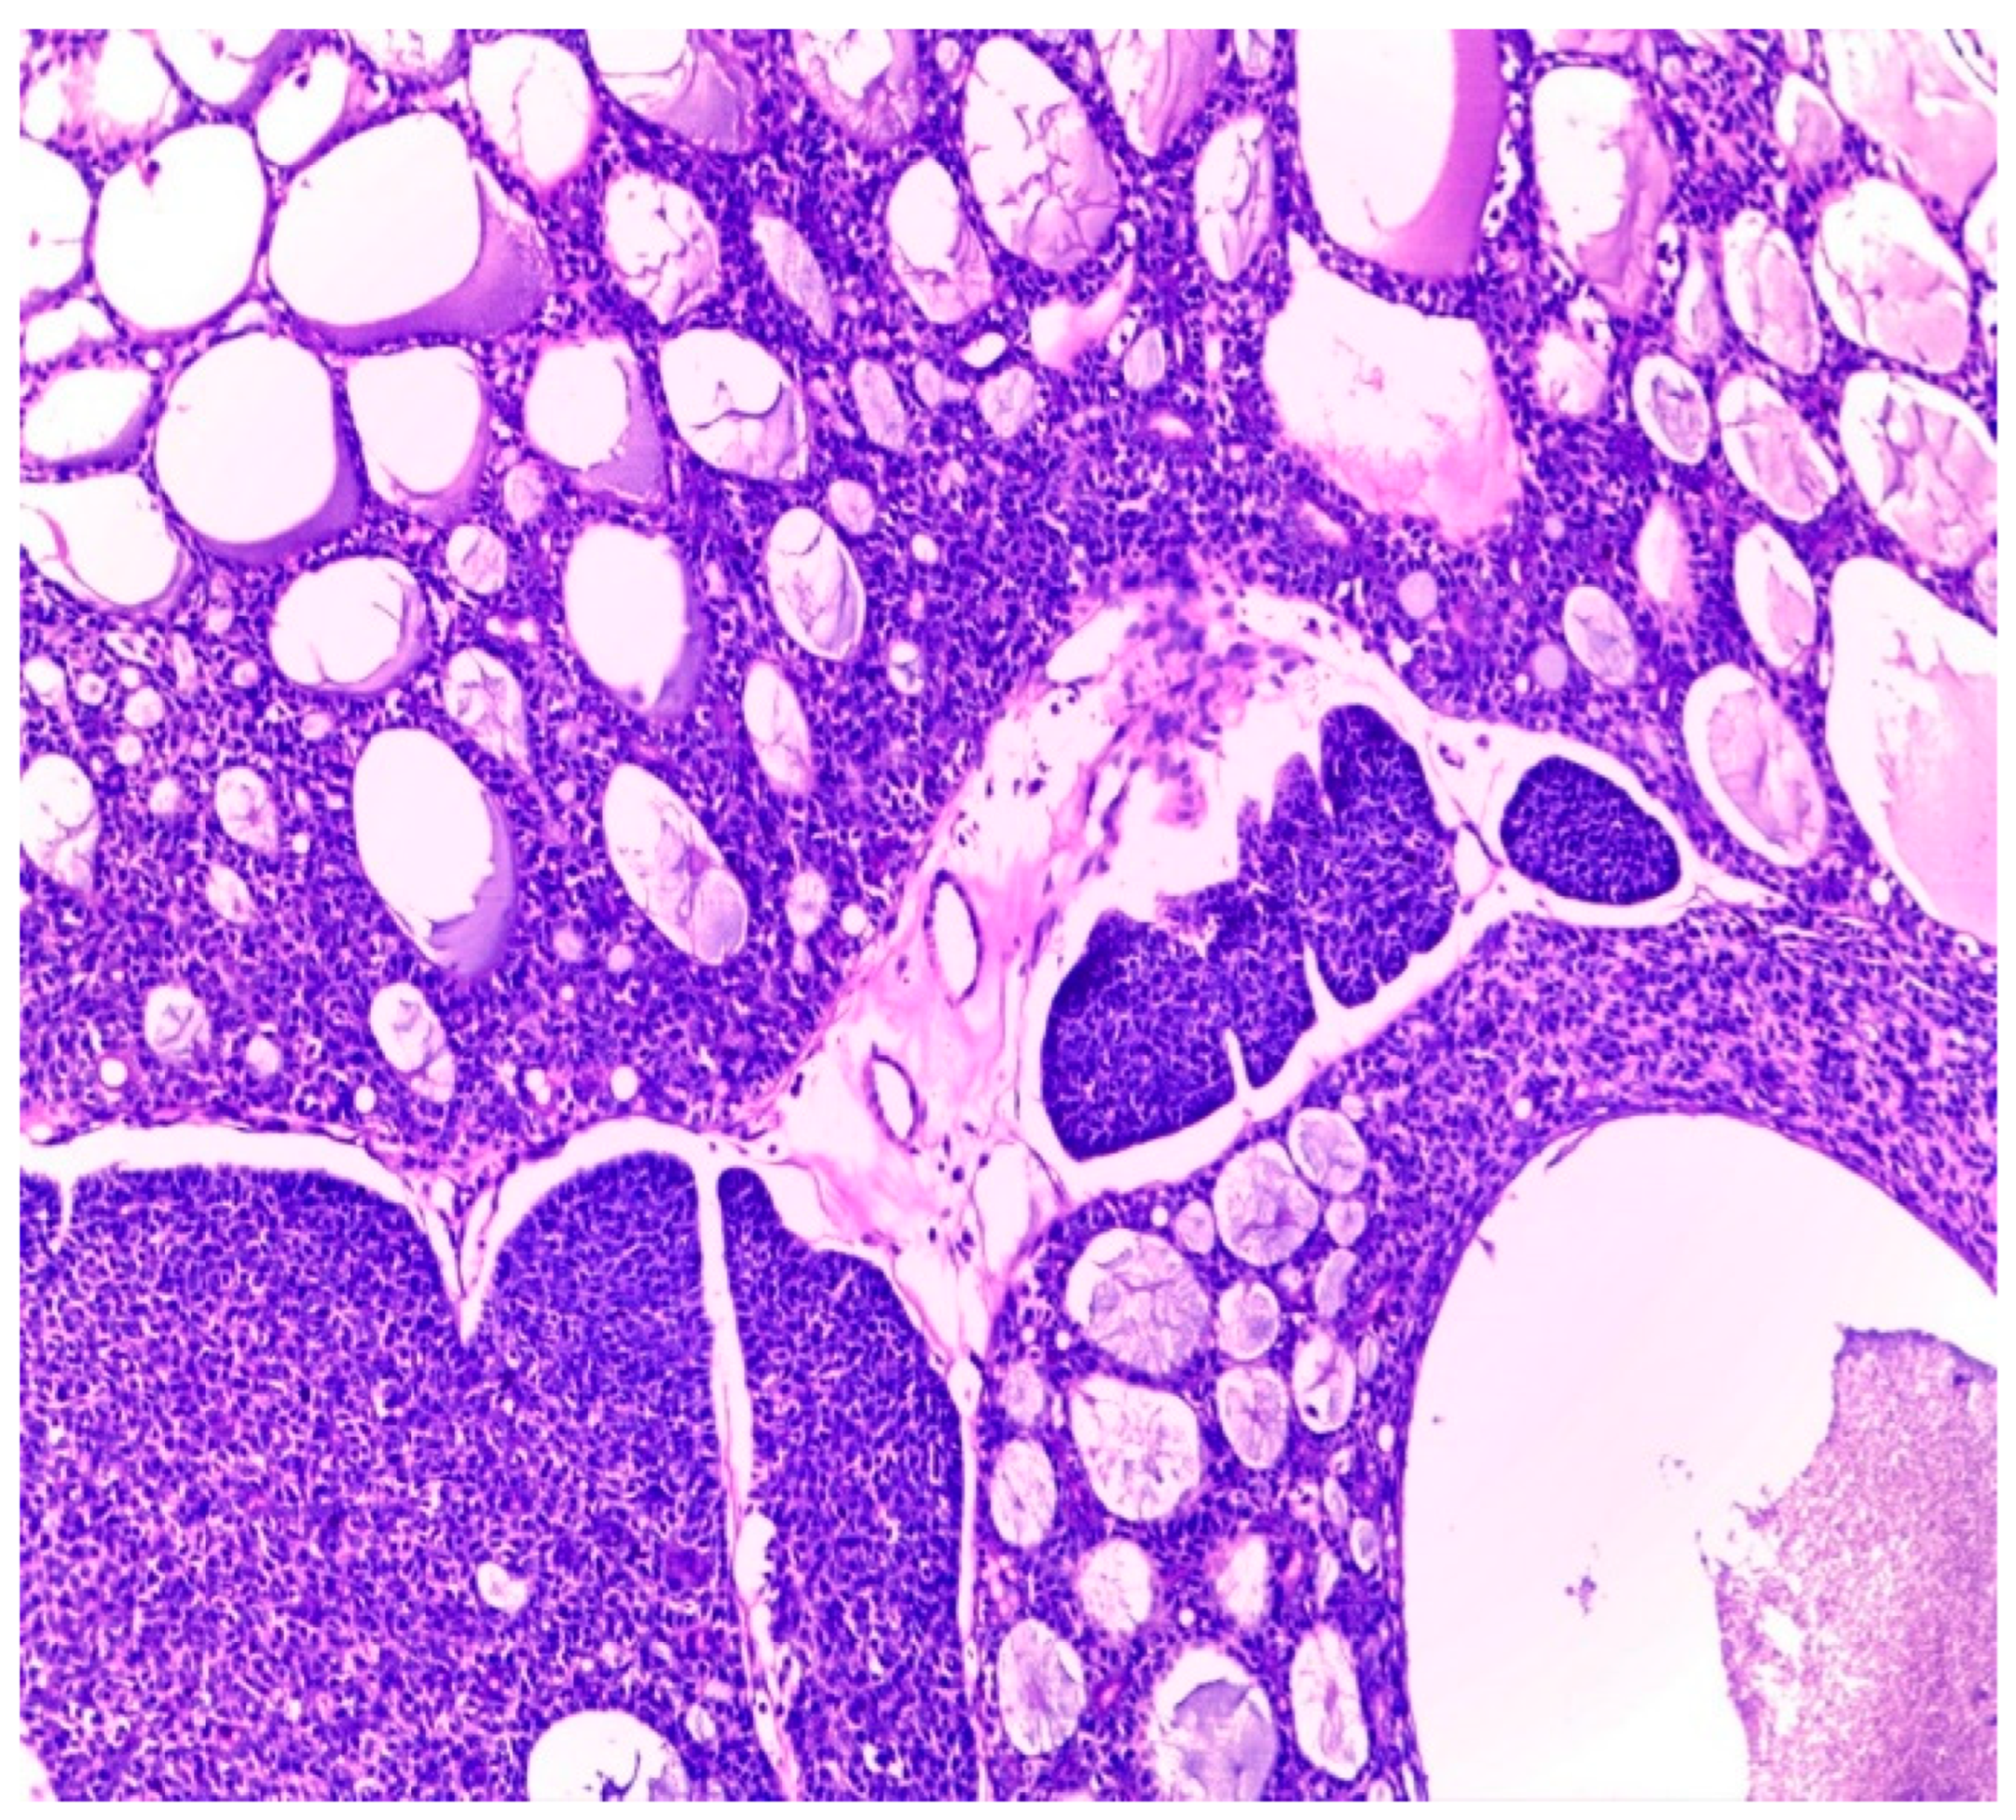

Histologically, salivary nonsolid AdCCs showed biphasic cell populations arranged in alternate cribriform and tubular architectures (Figure 1). The cribriform pattern demonstrated nests of neoplastic cells with hyperchromatic, angulated nuclei arranged in microcystic and macrocystic spaces. These pseudocystic cavities were occasionally filled with hyaline or basophilic mucoid material. The histologic features in the major salivary glands did not differ much from those in the minor salivary glands. However, solid nests of AdCC favored submucosal infiltration in the minor salivary glands (Figure 2, Case #15). Sinonasal AdCC revealed nests of cribriform and solid areas, while extensive hyalinization was recapitulating a jigsaw puzzle-like pattern (Figure 3). The cells of sinonasal AdCC were sometimes basaloid, with dark, hyperchromatic nuclei. The cells were typically arranged in a palisading pattern around the cystic spaces. A few salivary AdCCs revealed basaloid cells arranged in solid growth patterns that were insufficient for diagnosis as high-grade AdCCs. Mammary SB-AdCC revealed areas of cribriform, a solid growth pattern (>90%), and a basaloid appearance, with myxoid or hyalinized stroma. Ductules were present within the tumor islands. Small cysts and pseudoglandular structures were occasionally seen (Figure 4). This variant is characterized by the presence of small, basal-like cells with scant cytoplasm. The basaloid variant was associated with a higher risk of metastasis and a poorer prognosis. All neoplastic cells were positive for IHC SOX10, CK7, CD117, p63, and KI67. The clinical and molecular findings are shown in Table 1. There, all of the AdCC cases had MYB rearrangements detected by fluorescence in situ hybridization (FISH), which is a common genetic alteration observed in AdCC. Specifically, MYB was found to be fused with NFIB and/or KMT2C/KMT2D in AdCC cases from sinonasal and minor SG sites. MYB::NFIB fusion is a well-known molecular alteration that occurs in approximately 30–70% of AdCC cases and has been associated with better prognosis compared to cases without this fusion. On the other hand, MYB::KMT2C/D fusions were less common but have also been reported in cases from salivary and sinonasal AdCCs. Although this is the first study to report this finding, its clinical significance is yet to be fully elucidated. In addition to FISH, some AdCC cases were also analyzed using next-generation sequencing. In Table 1, NGS was performed in several AdCC cases from sinonasal, minor SG, and parotid gland sites. MYB::NFIB and MYB::KMT2D fusions were detected in these cases, which is consistent with the FISH results. Notably, some cases were not analyzable by NGS, which may be due to various reasons such as low DNA quality or quantity. The median score for Group 1 was 70 (IQR: 60–80), the median score for Group 2 was 85 (IQR: 75–90), and the median score for Group 3 was 60 (IQR: 55–70). The results indicate that there was a significant difference between Group 1 and Group 3 (p < 0.05) and between Group 2 and Group 3 (p < 0.05) but not between Group 1 and Group 2 (p > 0.05). This suggests that the solid mammary AdCCs with basaloid features (Group 3) have different characteristics compared to the other two groups.

Figure 4.

Mammary SB-AdCC revealed areas of cribriform, a solid growth pattern (>90%), and a basaloid appearance, with myxoid or hyalinized stroma. Ductules were present within the tumor islands (H&E stain; magnification ×5).